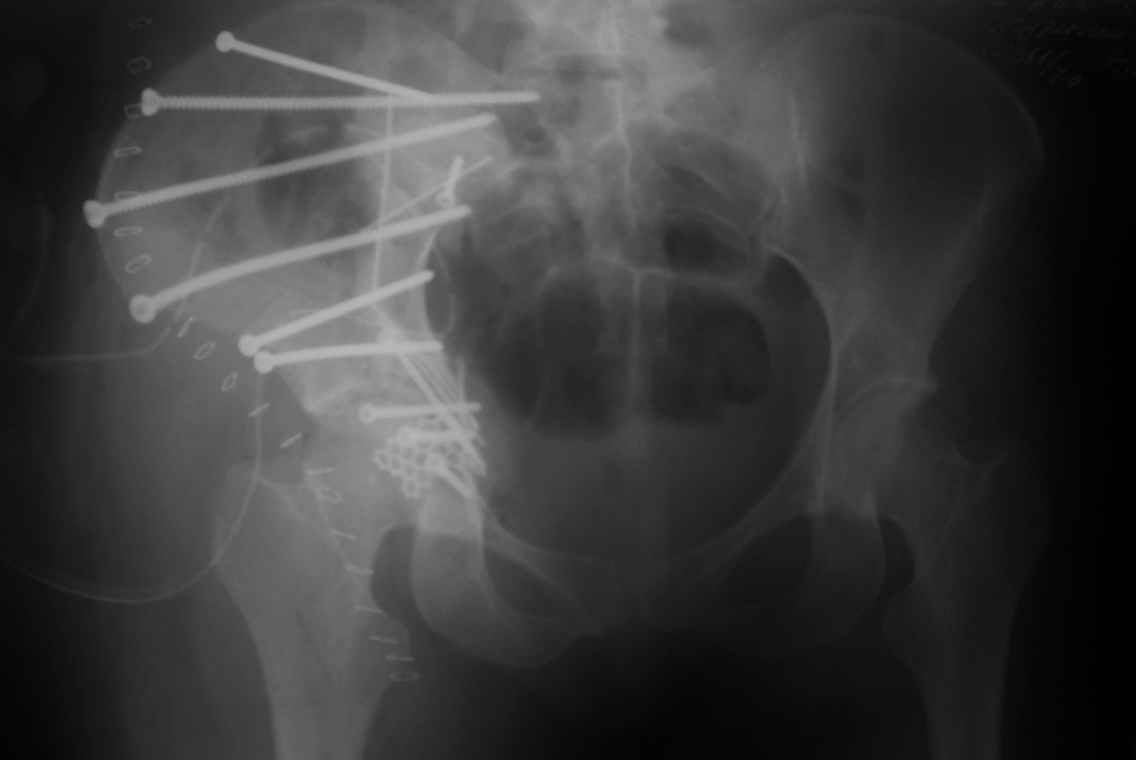

Вот еще одно наблюдение не совсем частое, большое желание поставить распорку поперек таза, чтобы вернуть конфигурацию тазового кольца.

Но считаю, что третий сорт не брак, тем более-то ноги одинаковые. Доступ между подвзлошно-паховым и подвздошно-бедренным, пришлось несколько расширяться книзу, но внимательно не посмотрел и попал на бедро, надо было все-таки по паховой складке, но вот беда - на хорошо загорелом теле не нашел следов более светлой кожи, поэтому рубец будет несколько выступать из под бикини. Посылаю три снимка. Пока. Вернусь через 10 дней. Жду ответа. ЛАФ.